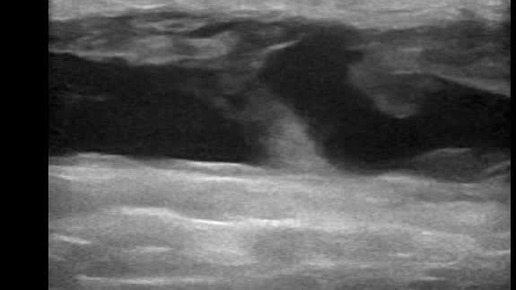

Видео к статье "Лизированная гематома бедра"https://dzen.ru/a/Z_NkYO9oFCnBP0Dc

Ультразвуковые находки от врача УЗД Зорина Я.П.